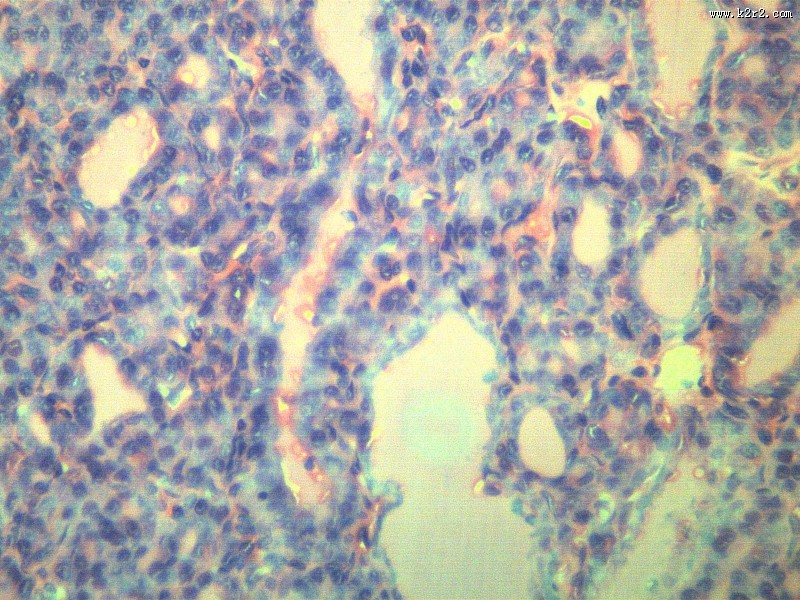

甲状腺瘤 - 第7张 共有

医学

显微切片

肿瘤

thyroidadenoma

甲状腺瘤

腺瘤